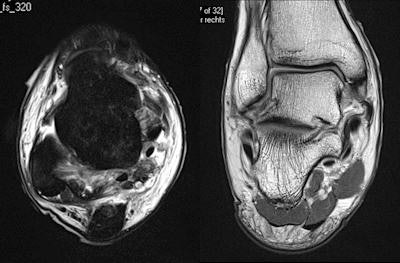

"Existe gran debate acerca de cuando es mejor obtener imágenes de lesiones en los tejidos blandos. El atleta lo desea inmediatamente o al menos dentro de las 24 horas. En mi experiencia, es mejor esperar unas 24 a 48 horas ya que de otra manera existe el riesgo de obtener un falso negativo," afirmo Healy, quien ayuda a cuidar a los atletas de varios clubes de football de Primera Liga y Liga de Campeones, así como también de equipos de rugby de Primera Liga, y quien ha estado involucrado en un estudio de lesiones de pierna-muslo de la Liga de Campeones desde 2007. "Si la imagen no correlaciona con los hallazgos clínicos, es entonces muy importante repetir la imagen. A menudo, si se obtiene la imagen muy temprano, se pierde la medida de lo que está sucediendo."

El Dr. Healy tiene una regla simple para determinar que modalidad debe usarse: si el paciente señala la anormalidad con un dedo, se debe empezar con ultrasonido; pero si el paciente la señala con la mano, se debe ir directamente a una imagen por RM. Además, el ultrasonido es mejor para obtener imágenes de estructuras superficiales, mientras que la RM es mejor para estructuras profundas.

Aun si el diagnóstico clínico es obvio, la obtención de imágenes se requiere para medir la extensión de la lesión y para identificar cualquier complicación. Si ha ocurrido una lesión significativa, la imagen es necesaria para asegurarse de que el diagnóstico inicial era correcto, afirmó Healy. Finalmente, las imágenes pueden ser benéficas para documentar la existencia, progresión o resolución de una enfermedad, lo cual puede ser útil por razones medico-legales.